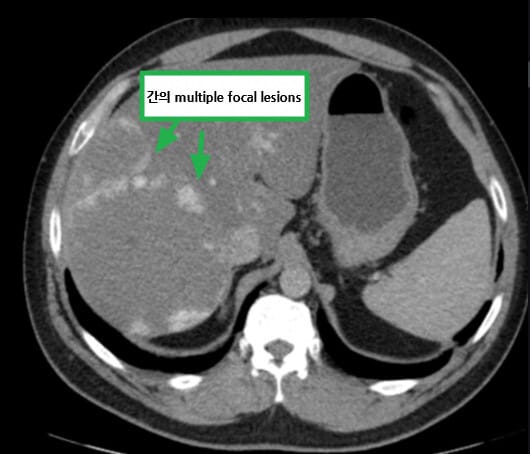

영상소견 정리

CT/ MRI 소견

조영증강 영상에서 고형성 종괴 + 중심 괴사, 혈관 침범

| ✅ 폐 또는 뼈 전이 |

| 흉부 CT에서 다발성 폐 결절, 골스캔에서 골 전이 소견이 있을 수 있습니다. |

| Stage IV (T4 또는 M1) |

| 종양이 인접 장기(부신, 대장 등)를 침범하거나, 원격 전이(폐, 뼈, 간 등)가 있는 경우. |

Stage IV

T4 또는 M1: 종양이 주변 장기 침범 또는 원격 전이가 있는 경우

| 💊 전신치료 (Systemic Therapy) |

| 1차 치료로 면역항암제 또는 표적치료제를 병합 또는 단독 사용합니다. |

| 💊 병합요법 |

| 예: Nivolumab + Ipilimumab 또는 Axitinib + Pembrolizumab 조합 |